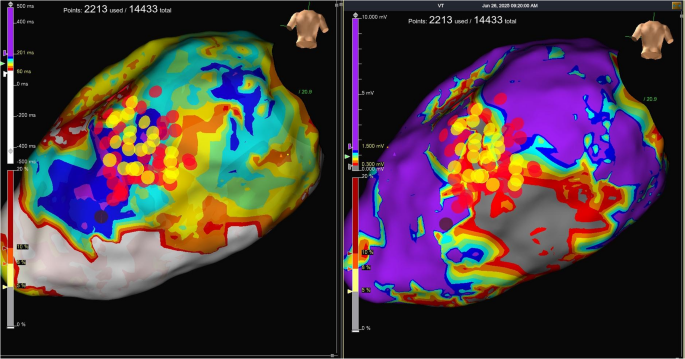

手术在全身麻醉下进行,通过左侧锁骨下静脉穿刺将LBBAP导管送入右心室。手术过程中使用LBBAP导管和三维弯曲传导导管进行引导。Tendril 2088TC 58厘米长的导线(St. Jude Medical)在确定正确的间隔穿刺位置(距离心尖和心底等距)后,通过LBBAP方法进行插入,并持续监测12导联QRS波形和单极阻抗。通过不透明造影剂确认导管位于室间隔边缘(视频1)。

为了降低动脉损伤的风险,在通过左前降支(LAD)的间隔分支时,通过插入左主干冠状动脉(LMCA)开口的6F Judkins导管注入不透明造影剂来进行可视化观察(视频2,图2)。在间隔映射过程中,当以100毫米/秒的频率进行起搏时,在V1导联观察到W形波形(图3